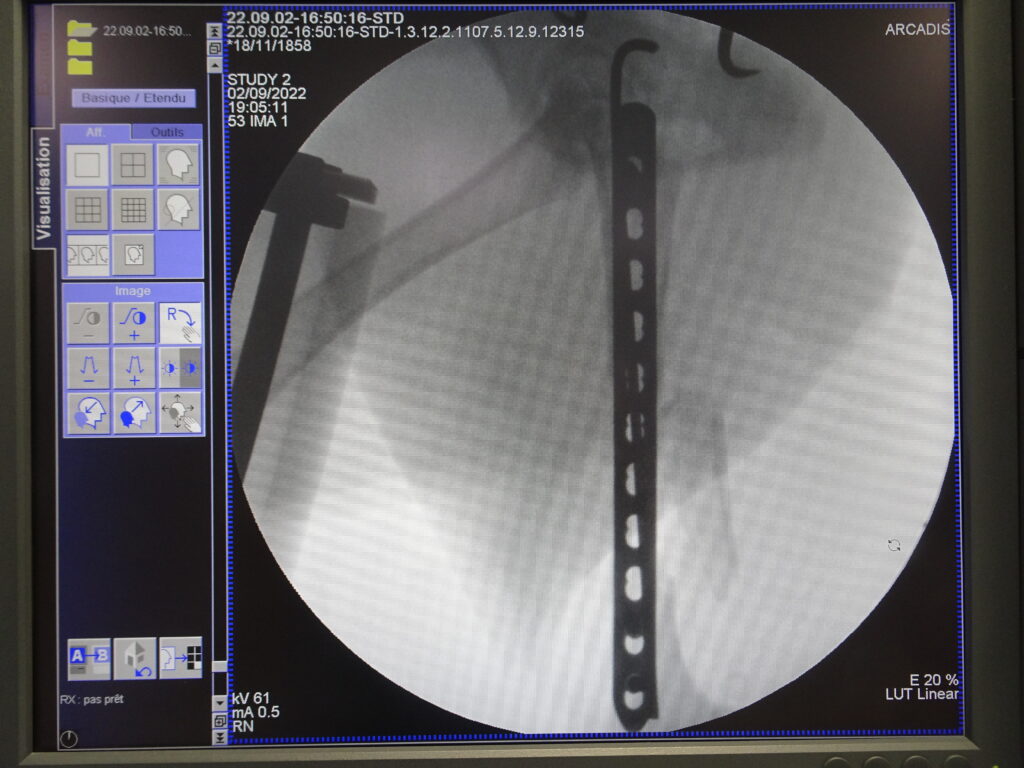

Stabilisation d’une fracture du fémur par voie mini invasive grâce à la fluoroscopie.